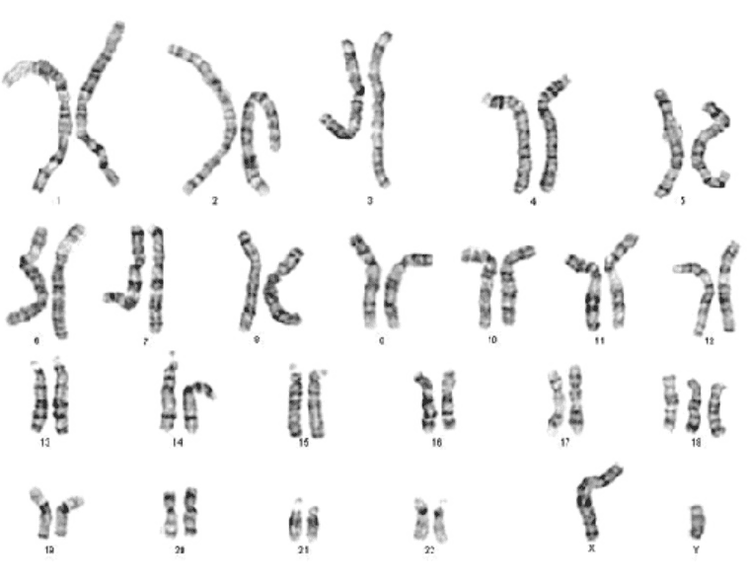

3. Bất thường nhiễm sắc thể liên quan đến ARSA như thế nào?

Nhiễm sắc thể là nơi lưu giữ thông tin di truyền của chúng ta. Chúng ta có 46 nhiễm sắc thể xếp theo cặp: 23 đến từ bố và 23 đến từ mẹ.

Ví dụ, người mang hội chứng Down có thêm một nhiễm sắc thể 21. Người mang hội chứng DiGeorge có thay đổi thông tin ở một trong số các nhiễm sắc thể 22. Cả hai tình trạng trên khá thường gặp ở em bé có ARSA; nếu thay đổi thông tin trong nhiễm sắc thể xảy ra, nó sẽ là nguyên nhân của ARSA. Tuy nhiên, trong hầu hết các trường hợp ARSA, không tìm thấy bất thường nhiễm sắc thể hoặc nguyên nhân di truyền.

Khi ARSA được xác định trên siêu âm thai, bạn cần được siêu âm chi tiết hình thái thai nhi, đặc biệt là tim và các mạch máu. Nếu ARSA là đơn độc và không có bất thường giải phẫu nào được ghi nhận thêm, bạn có thể sẽ không cần làm xét nghiệm gì thêm. Tuy nhiên, nếu phát hiện có nghi ngờ gì khác, bạn cần được tư vấn di truyền và làm các xét nghiệm di truyền, để loại trừ các bất thường nhiễm sắc thể có thể xảy ra cho em bé, như hội chứng Down và hội chứng DiGeorge.